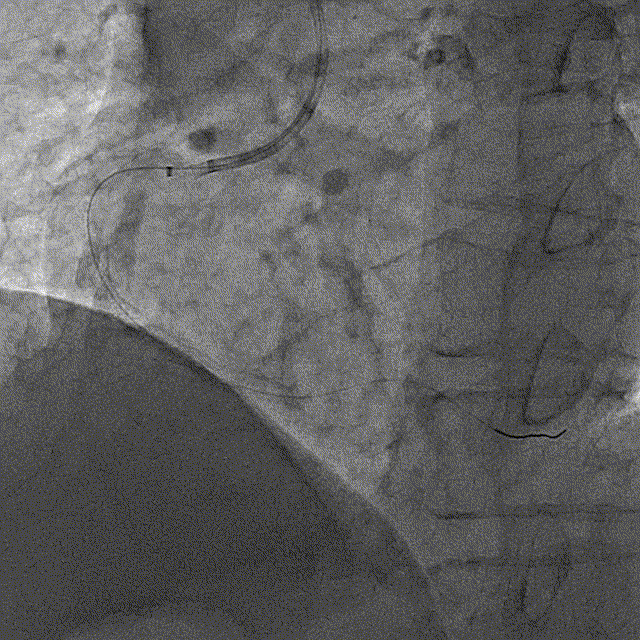

冠脉内介入治疗